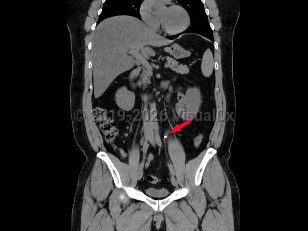

Ureteral calculus

While many stones located within the renal pelvis are discovered incidentally on radiographic or sonographic imaging, most stones that have passed into the ureter and are of significant size cause renal colic. Renal colic is sudden-onset flank pain radiating to the groin, accompanied by nausea and vomiting. This colicky pain typically waxes over the course of 15-30 minutes and becomes steady, unrelenting, and unbearable. Patients may experience worsening paroxysms of pain lasting 20-60 minutes as the stone courses downward through the ureter and as the ureter spasms.

If the stone's descent is arrested at the ureterovesical junction, patients may experience urinary frequency, dysuria, and urgency and are predisposed to the development of urinary tract infections both from the stone forming as a nidus for bacterial growth and from the mechanical urothelial trauma caused by the stone's movement. Most individuals with nephrolithiasis will also develop hematuria, particularly when passing a stone.

Pain from nephrolithiasis is thought to primarily be the result of renal capsular distention and varies depending on the location of the stone and the degree of obstruction caused by the stone. Stones that occlude the upper ureter or ureteropelvic junction invariably cause significant flank pain that is accompanied by severe costovertebral angle tenderness to palpation. As the innervation of the testicle is shared with the kidney, patients often describe radiation to the testicles or labia. When stones pass into the bladder, patients usually experience swift resolution of their pain.